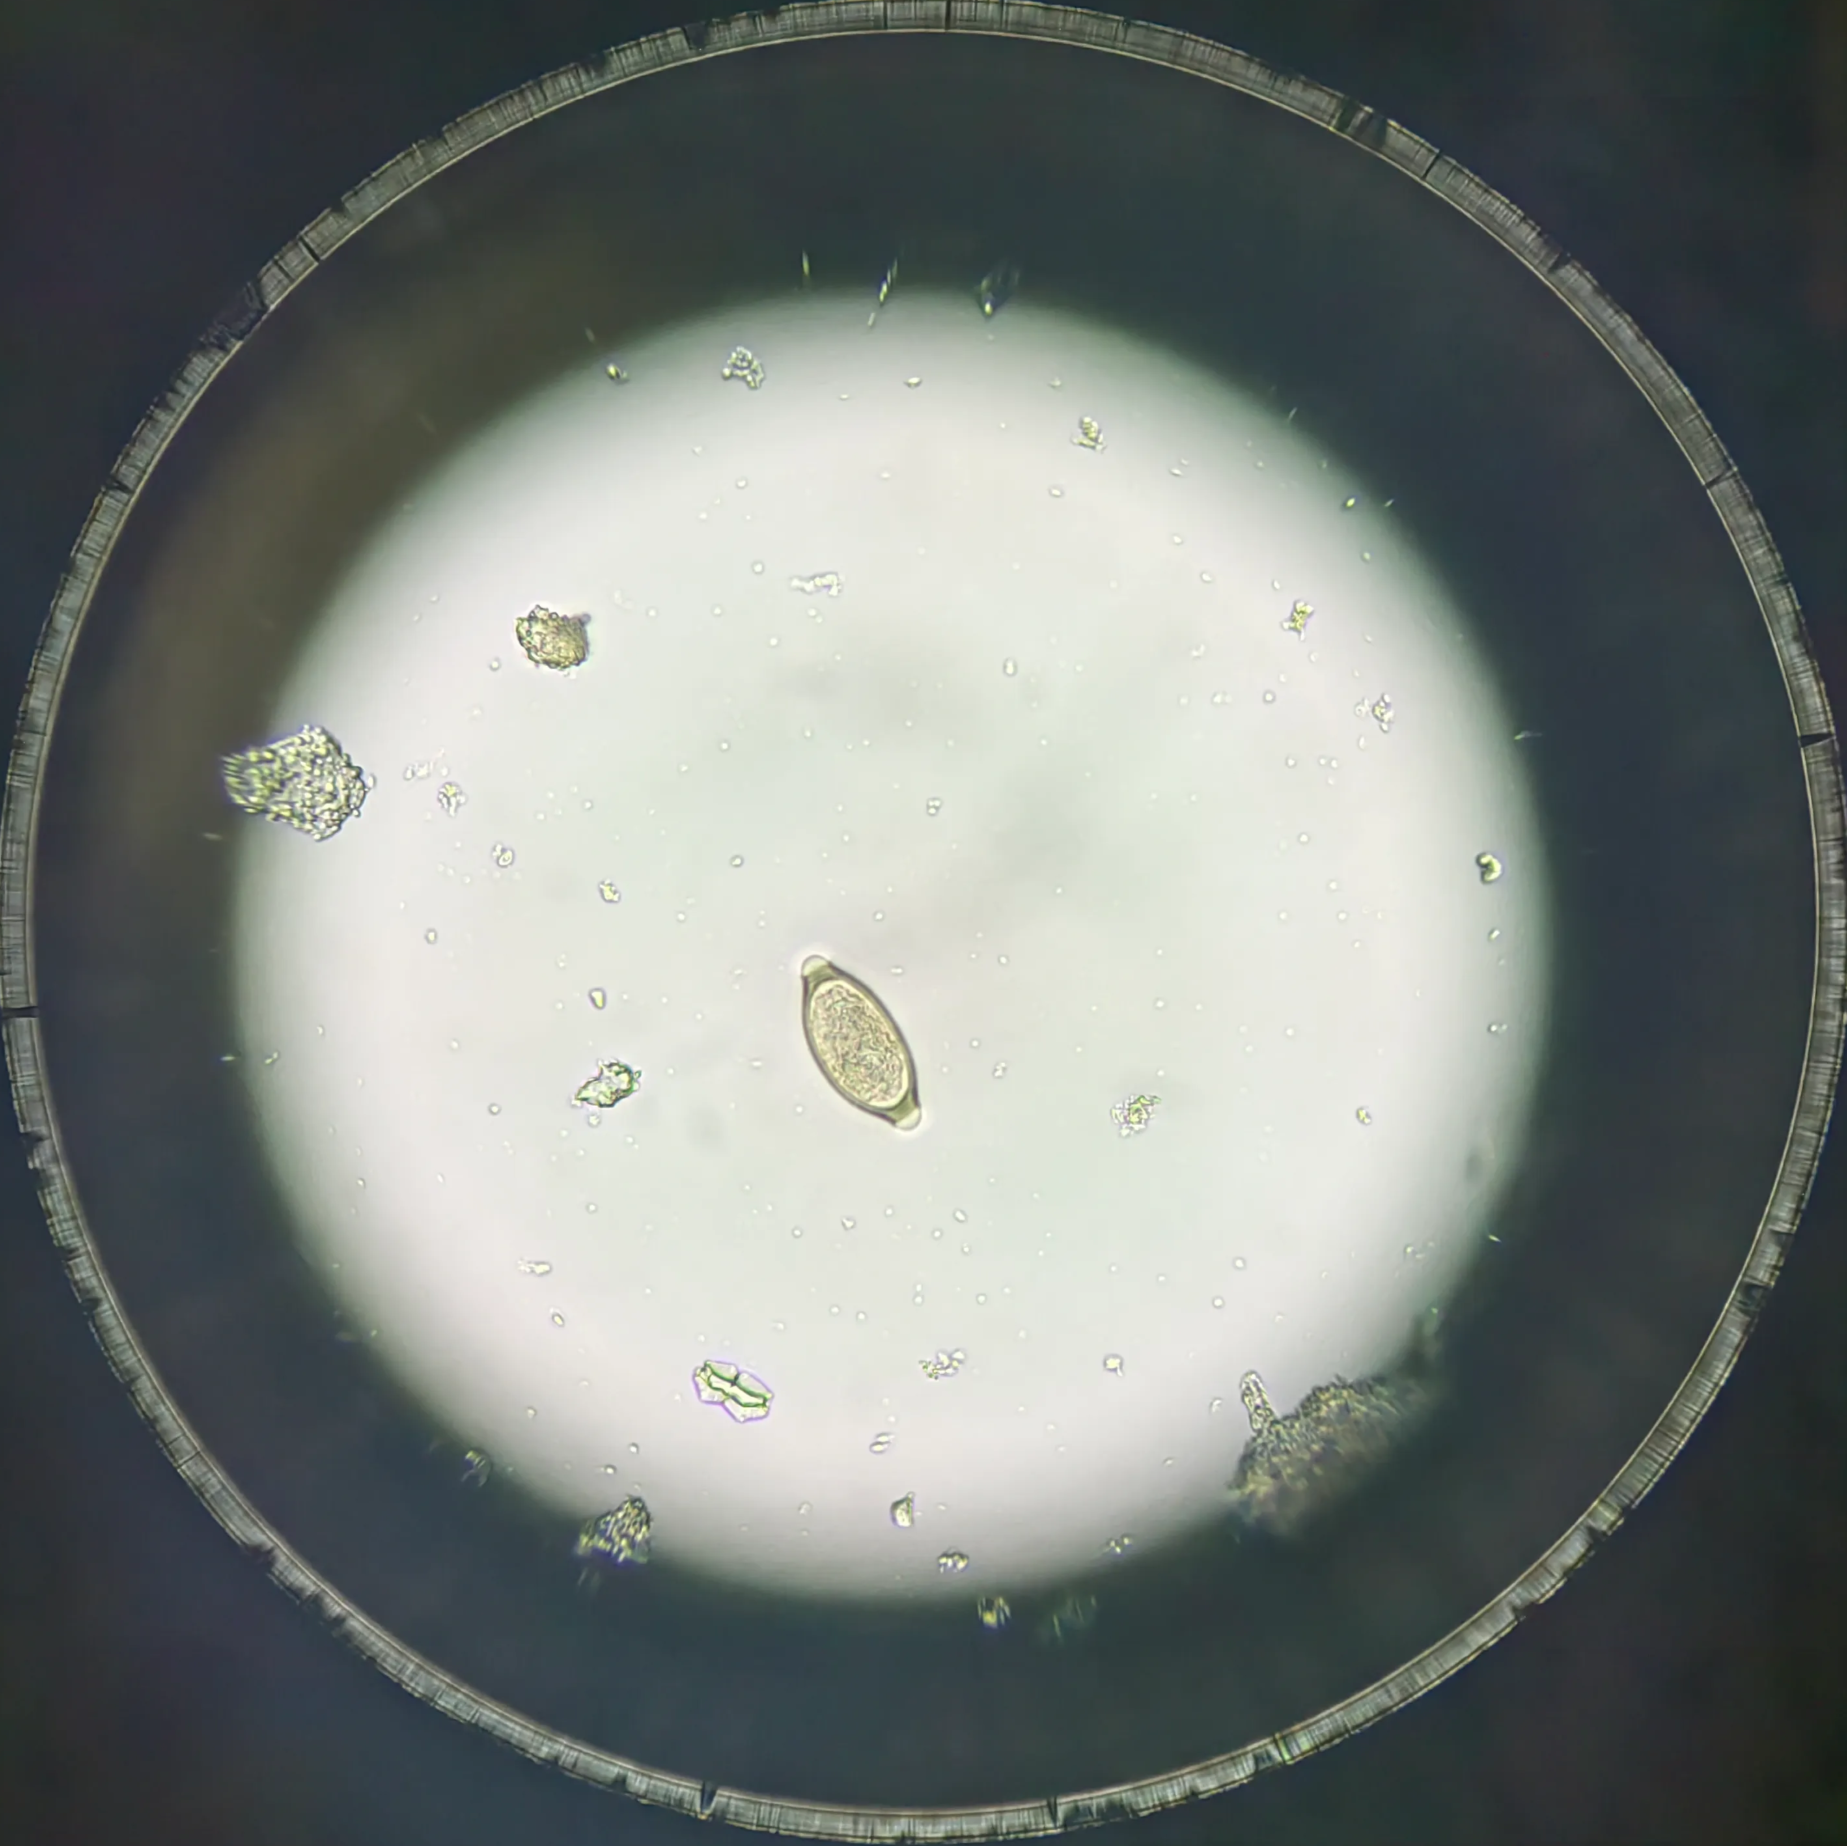

受精蛔虫卵

受精卵呈宽椭圆形,大小为(45~75) m×(35~50)wm。卵壳较厚。卵壳外常有一层由子宫分泌物形成的凹凸不平的蛋白质膜,被宿主胆汁染成棕黄色,卵内含有1个大而圆的受精卵细胞,在其两端与卵壳间可见新月形空隙。